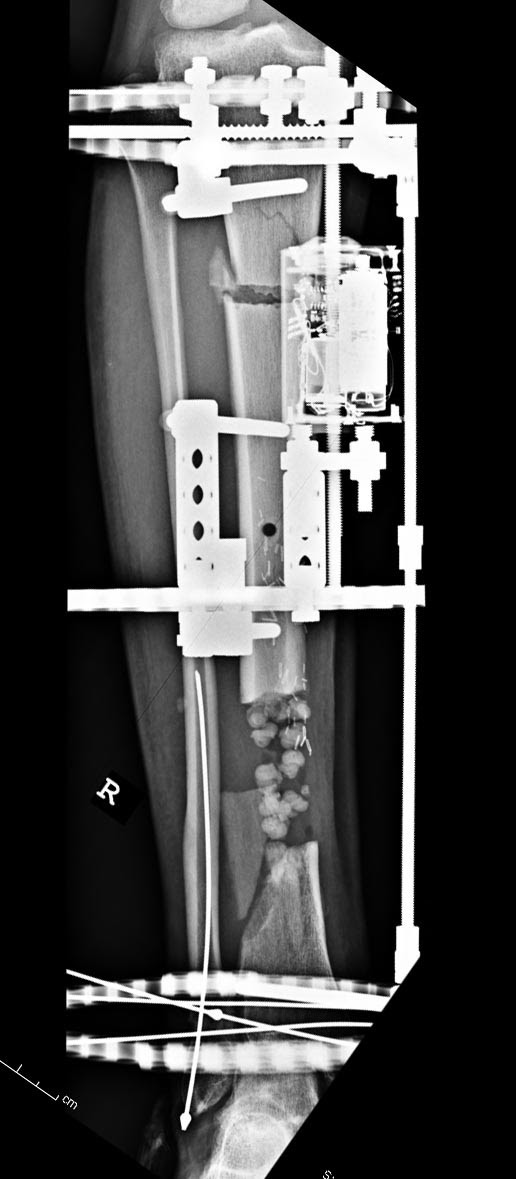

Данный случай не огнестрельная рана, а результат мотоциклетной аварии.

Независимо от повреждения при таких обширных дефектах мягких и костной

тканей применяется схожая тактика. Как видно, после нескольких I&D для

создания “pseudo membrane” применили цилиндрический блок из цемента.

Дефект мягких тканей закрыли свободным Anterior Thigh Graft. Из малого

доступа цилиндр удален небольшими кусочками, а пространство заполнили

бусами для освобождения пространства. По мере приближения регенерата

освободили пространство удалением бус через небольшой разрез. Этап

созревание регенерата можно было ускорить усилением интрамедуллярным

гвоздем, но решили закончить методом Илизарова.